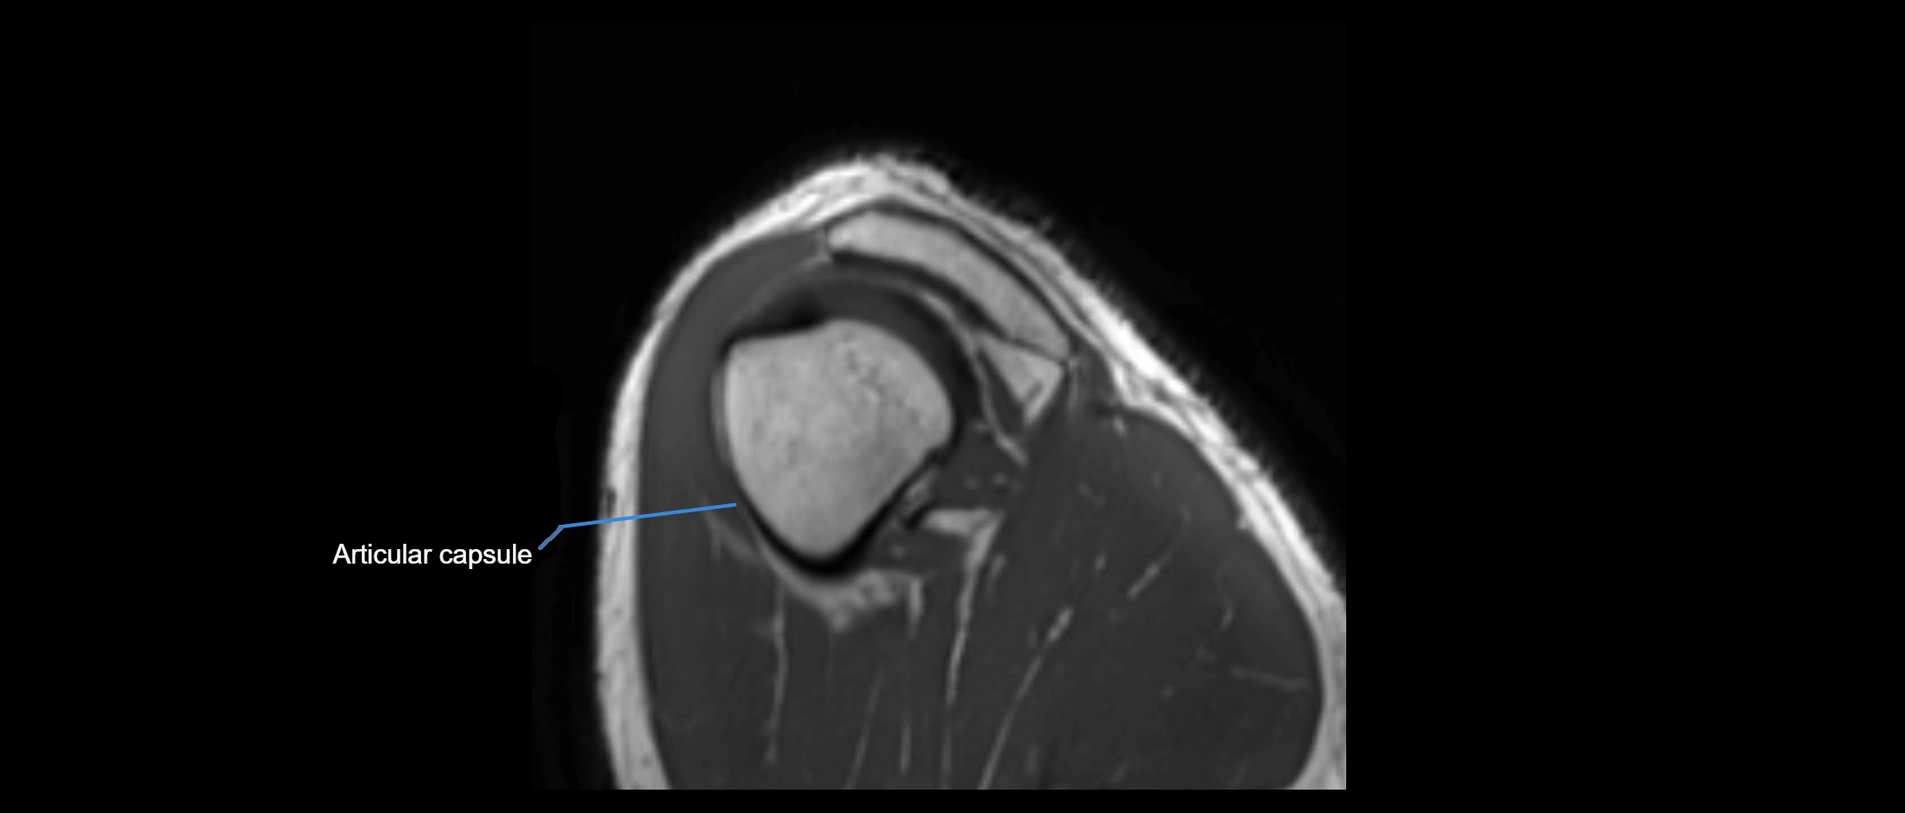

CT image

image

CT Appearance

Non-Contrast CT:

• Ligament: Not directly visualized due to small size and low density.

• Bony landmarks: Lateral clavicle and acromion clearly seen; cortical margins well defined.

• Pathology: Detects fractures, joint subluxation, osteophytes, and degenerative changes.

• Alignment assessment: Evaluates AC joint spacing and clavicular displacement.